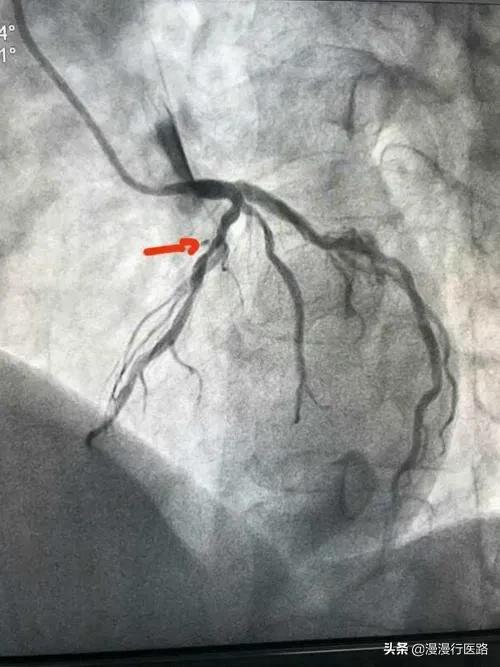

Après plusieurs tentatives de persuasion, Lao Fu a été hospitalisé et j'ai fait en sorte que Lao Fu passe un cardiogramme, qui a révélé qu'un vaisseau sanguin du côté gauche était rétréci à 99 % et immédiatement bloqué, grâce à une détection opportune. Cependant, un stent domestique coûte 7 500 euros, et les autres instruments chirurgicaux des dizaines de milliers d'euros. Pour une famille comme celle de Lao Fu, c'est un véritable fardeau. Il se trouve que le Dr Wang était responsable d'une expérience, à savoir une étude clinique sur le processus de pose de stent, et il a demandé à Lao Fu s'il était prêt à participer à l'étude, afin qu'un stent lui soit posé gratuitement. Lao Fu a accepté avec plaisir, car après tout, cela lui permettrait d'économiser près de 10 000 yuans. Lorsqu'il a renvoyé Lao Fu au service, celui-ci avait toujours l'air inquiet et lui a demandé ce qui n'allait pas.

J'ai alors fait procéder aux examens nécessaires et l'imagerie a montré que la sténose de l'artère coronaire gauche atteignait 85 %, ce qui nécessitait la pose d'un stent.

J'ai expliqué à M. Zhang : "M. Zhang, le degré de sténose de votre artère coronaire gauche a atteint 85%, et la dernière comparaison est manifestement sérieuse, pour répondre aux critères de mise en place de stents, vous devez l'envisager".